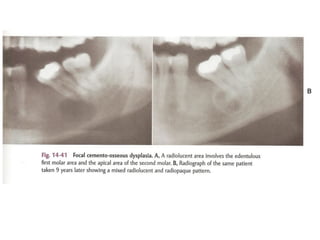

Periapical cemento-osseous dysplasia